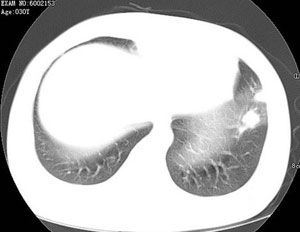

女性,30岁。

病史为胸痛20多天,无畏寒发热,无消瘦,无咳嗽咳痰。总之症状很逍遥。

临床以胸痛待查收住入院。

双肺野可见散在大小不等结节及肿块影,内密度不均匀,边缘部分清,部分欠清,纵隔未见明显肿大淋巴结.右侧胸腔少理积液.结合临床,考虑韦格肉芽肿可能吧,巨淋巴增生,结节病,特殊感染都要考虑.转移瘤临床不象.

本病例特点如下:

1.青年女性,以胸痛20多天就诊,无呼吸道及感染临床症状体征,无原发肿瘤病史;

2.肺ct表现为两肺多发大小不等结节影,大结节位于肺尖部,小结节多位于肺外带胸膜下,大结节内可见支气管充气征,周围可见月晕征(指在结节状或肉芽肿样病灶周围呈环形磨玻璃影),右肺门及腔静脉后可见小淋巴结,右侧胸腔内少量液体。

两肺散在分布大小不等的肿块及结节影,边缘毛糙,有分叶、毛刺,病灶密度不均匀,可见支气管充气相与空泡征。病变大多位于胸膜下,可见胸膜凹陷及胸腔积液。气管腔静脉间可见小结节影。